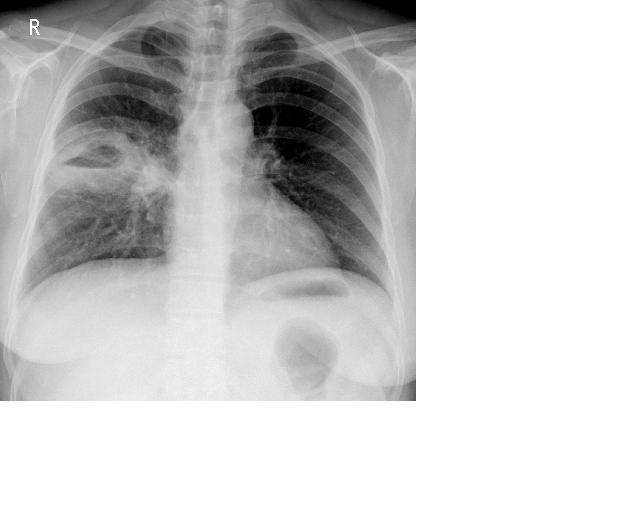

治疗12天后复查:

如果是抗炎治疗后查:病灶明显减小。支持肺脓疡。